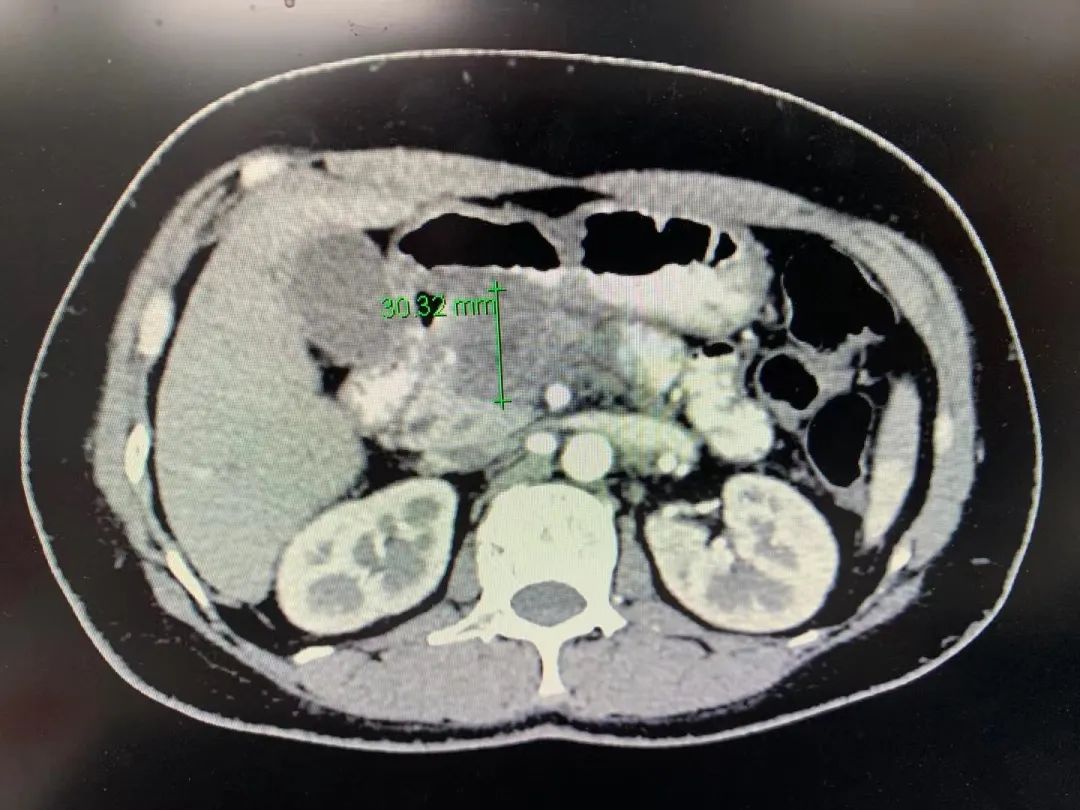

随后,秦女士在新桥医院肝胆外科二病区经新辅助化疗3周期以后,肿瘤情况明显好转,肿瘤直径从62.49mm缩小至30.32mm,腹腔干显露,肝总动脉周围肿瘤侵犯情况好转,肠系膜上动脉周围侵犯淋巴结明显缩小,肿瘤标志物Ca199也降至18.6 U/mL,恢复正常值范围。

▲新辅助化疗3周期后肿瘤情况